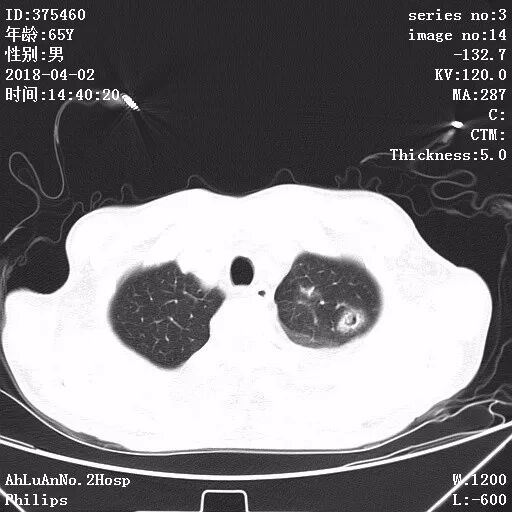

患者男,65岁,因“咳嗽、咳痰1月余,发热1周”入院。

两肺可见多发斑片状及气囊样阴影,部分气囊样影内可见气液平面,两侧胸膜腔可见少量液性密度影聚集。

结果:金黄色葡萄球菌肺炎

显示,白细胞计数和中性粒细胞百分比升高,可有核左移及中毒颗粒。本病的胸部X线特征常表现为肺段或肺叶实变,或呈小叶样浸润,其中有单个或多发的液气囊腔。

X线阴影的易变性是本病的另一重要特征,其常表现为一处炎性浸润消失而在另一处出现新的病灶,或很小的单一病灶发展为大片阴影。